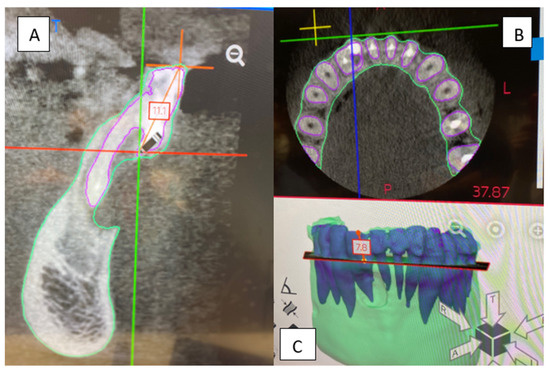

- The comparison between the use of 3D printing and milling with the use of Materialise software, as used in the current study, was profiled in a study by Kachhara et al. They concluded that an exact tooth replica can be created to assist in treatment planning [26]. The ability of the clinician to view a 3D model versus manipulating a CBCT image in the axial, sagittal, and coronal views, is beneficial to appreciating the fine detail of the unique root anatomy. The exact replica is produced to a high level of detail that can be directly viewed. Being able to handle the physical model provides an opportunity to manipulate and observe the model and appreciate the unique characteristics of the tooth and root anatomy when conceptualizing the proposed nonsurgical and surgical endodontic treatment.

- The use of two PRF membranes made several significant contributions to treatment execution. The soft, flexible nature of PRF is ideal for layering over MTA without adversely affecting the surface texture. The first membrane delicately smoothed and contained the material within the confines of the DI during the setting period. The second PRF membrane was used to protect the entire defect and to retain the grafting particulate and maintain its osteoconductive properties, enabling the ingrowth of vascular and cellular connective tissues. The PRF in grafting gives the advantage of using the patient’s blood products to maximize available growth factors and to dramatically improve the speed of osseous healing [8,27,28]. For DIs with a wide, oblique foramen, PRF is critical to retaining and protecting the MTA filling while providing the above-mentioned healing benefits. The present case report demonstrated that using 3D models led to improved pretreatment planning and provided a more accurate protocol for the surgical intervention.